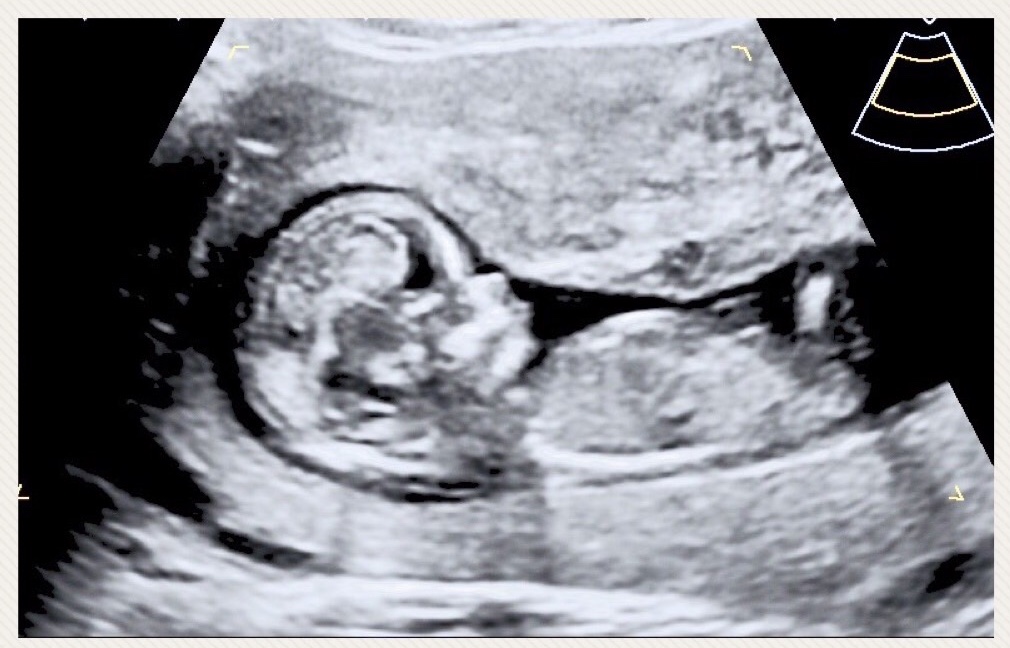

I am still in total shock......I never thought this would be me. Confirmed girl at 16+1Attachment 40150